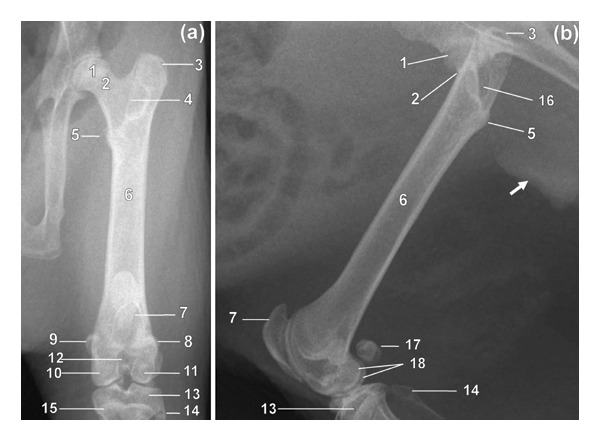

3.2. Femur

On the CdCr and ML views, the femur was fairly straight and slender (Figure 2). The diaphyseal cortices were almost of the same width (Figure 2). The medially directed femoral head was more or less rounded (Figure 2). The femoral neck was distinct and relatively long (Figure 2). The major trochanter was prominent and extended proximally higher than the femoral head (Figure 2). The caudomedially positioned minor trochanter was less prominent (Figure 2). Intertrochanteric crest connected minor and major trochanters (Figure 2). The former was visualised as a thin line of bone opacity slanting from proximolateral to distomedial on the CdCr view (Figure 2(a)). The third trochanter was not visualised (Figure 2).